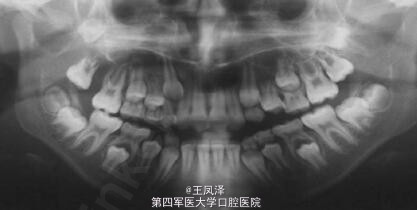

患者女,9 岁,发现右侧上颌骨无痛性肿块 3 个月余。查体见右侧上颌骨明显肿胀,质硬,不可活动,触之无疼痛感,约 3 cm× 2 cm 大小。肿块自右侧颊部向右侧腭部膨隆,右侧上颌牙齿移位,I 度松动。余未见明显异常